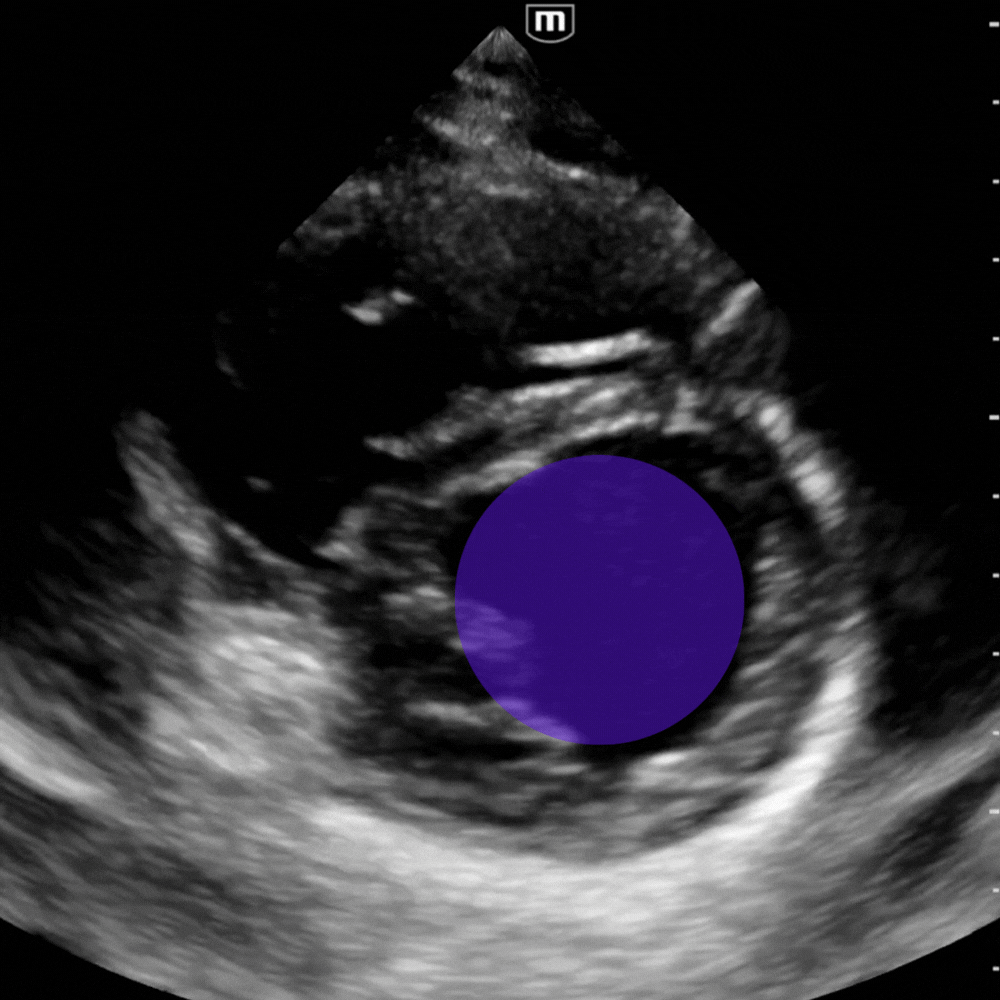

Parasternal petit axe → Cinétique pariétale

En parasternal petit axe, identifiez les anomalies de la cinétique pariétale en recherchant une asymétrie de contraction entre les différents segments du ventricule gauche. A noter que la contraction concentrique du VG est symétrique et harmonieuse, chaque segment se rapprochant de façon égale du repère circulaire central (video ci-dessous).